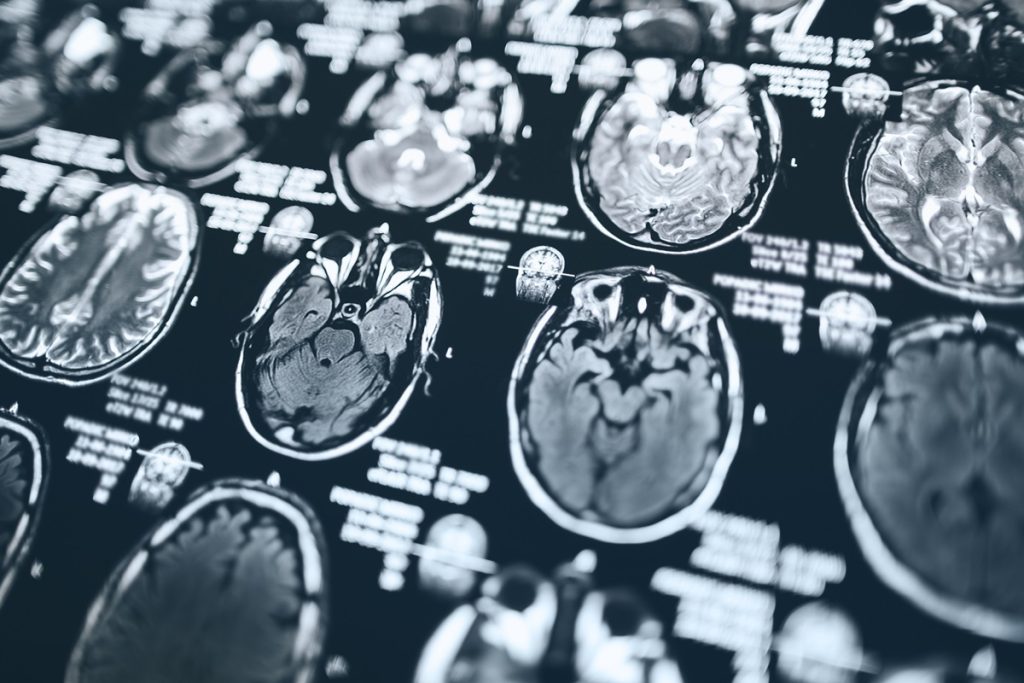

O acidente vascular cerebral, também conhecido como AVC ou derrame cerebral, é a interrupção do fluxo de sangue para alguma região do cérebro

O acidente pode ocorrer por diversos motivos, como acúmulos de placas de gordura ou formação de um coágulo – que dão origem ao AVC isquêmico –, sangramento por pressão alta e até ruptura de um aneurisma – causando o AVC hemorrágico

Muitos sintomas são comuns aos acidentes vasculares isquêmicos e hemorrágicos, como: dor de cabeça muito forte, fraqueza ou dormência em alguma parte do corpo, paralisia e perda súbita da fala